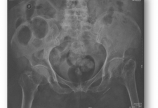

李某,女,汉族,81岁,某厂退休工人,75kg。走平路时跌倒致左髋部疼痛、活动受限10天。患者10天前散步时,因躲闪对面行人不慎跌倒致左侧肢体着地,当即感到左髋部疼痛、站立和行走困难。摔倒时无昏迷、恶心呕吐、胸腹腰部疼痛二便失禁等。卧床休息数日后,疼痛未见减轻,且不能站立,于附近诊所拍X线片示:“左股骨颈骨折”为进一步治疗来我院就诊。受伤以来,患者精神好、神志清楚,生命体征平稳,饮食及二便正常。辅助检查:实验室检查:血常规:RBC2.0×10E12/L    HGB85g/L    WBC6.44×10E12/L离   子:钠128.0mmol/L    氯90.4mmol/L   钙2.2mmol/L血   糖:空腹6.2mmol/L血   凝:D-二聚体18.45mg/L   A L P  : 148 U/LX线片:Garden III型下肢血管彩超:左股浅、腘静脉血栓形成(完全充填型)BMD检查:诊断与鉴别:左股骨颈骨折   左下肢静脉血栓形成   高血压病I级   胆囊摘除术后   骨质疏松症